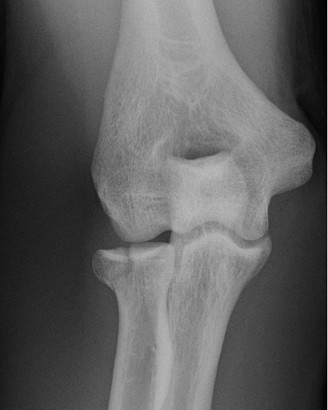

Examination reveals deformity about the elbow with no open lesions or skin tenting. He has a palpable radial and ulnar pulse and is neurologically intact. His images are shown (Figs. 2–85 to 2–88).

Figure 2–85

Figure 2–86

Figure 2–87

Figure 2–88

What is the diagnosis and direction of displacement?

Discussion

The correct answer is (B). This is the most common type of elbow dislocation, and often does not cause any osseous injury. Posterolateral and posteromedial dislocation account for approximately 90% of dislocations. Adequate pre- and postreduction films are necessary to evaluate for fracture, which would change the classification to a complex injury.